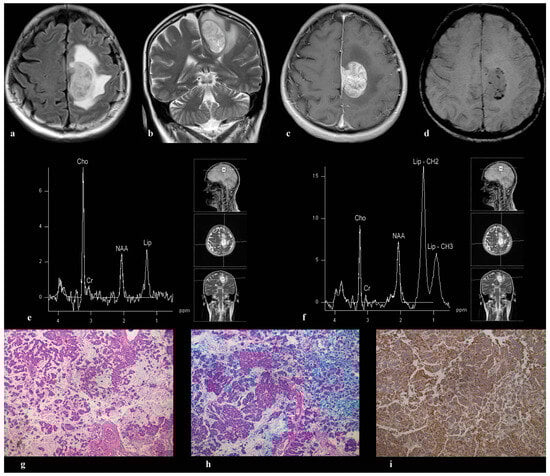

3.4. Patient 4